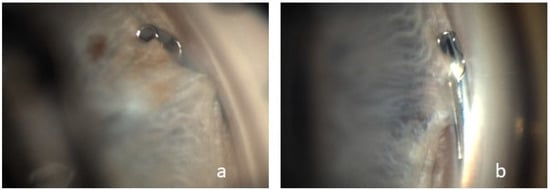

Peripheral synechiae between the iris and the implant without obstruction was observed in four cases (Figure 3).

Peripheral anterior synechiae with device occlusion was reported as a cumulative event in 3.5 cases at two years and 5.4 cases at five years. As in the prospective, randomized study by Pfeiffer et al. and in the COMPARE study by Ahmed et al., we were able to demonstrate the formation of focal peripheral anterior synechiae, which is also listed in the Hydrus® Manual as the most frequent complication of combined MIGS and cataract surgery with a prevalence of 40% [5,22,23]. Pfeiffer et al. followed their patients for 2 years and reported synechiae in 12% of their patients in the first year, increasing to 18.8% in the second year [22]. In our study with a shorter follow-up, there were four cases in which we observed peripheral synechiae in the proximal inlet area. The patients in our study cohort in whom synechiae formation was visualized were examined by 360-degree gonioscopy at a mean interval of 278.25 days, suggesting that synechiae formation may increase in the postoperative course. In addition to synechiae formation, Ahmed et al. described tissue adhesions to the iris as a postoperative side effect, which in one patient had to be removed by yttrium–aluminum–garnet laser treatment. In none of these cases did the IOP evolution indicate implant occlusion [8]. None of the eyes included in our study required secondary surgical intervention.

Figure 4. Visualization of two cases (a,b) of peripheral synechiae between the iris and the proximal tip of the Hydrus® Microstent.